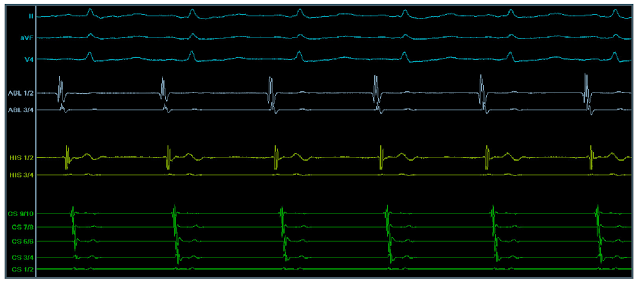

Intrakardiální EKG je grafický záznam srdeční elektrické aktivity, jenž je snímán pomocí do srdce zavedených katétrů. V tabulce 1.1 jsou uvedeny délky základních intervalů na intrakardiálním EKG při sinusovém rytmu.

Fyziologický sinusový rytmus na intrakardiálním EKG je znázorněn na obrázku 1.1 při rychlosti posunu 100 mm/s. První 3 svody shora obrázku jsou záznamy z povrchového EKG, signály označeny jako ABL pocházejí z ablačního katétru, katétr s označením HIS snímá signály z Hisova svazku a 10-polární katétr CS je zaveden do koronárního sinu, který se nachází mezi levou síní a levou komorou a ústí do pravé síně.

| Obrázek 1.1: Ukázka sinusového rytmu na intrakardiálním EKG. |